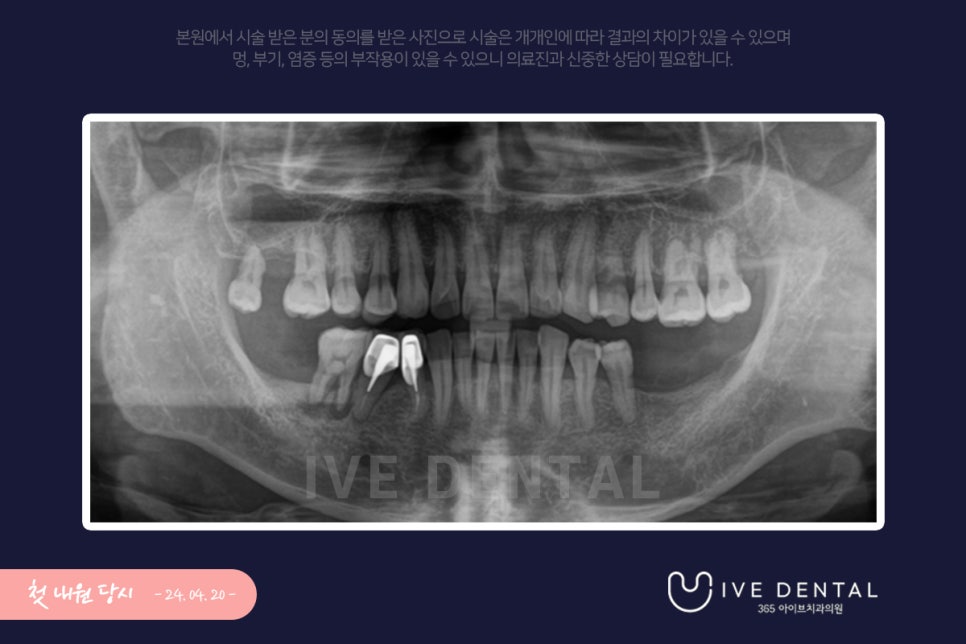

내원 시 파노라마 사진입니다.

전체적으로 잇몸 상태가 좋지 않아 염증이 심하고 치아가 흔들리며 통증이 지속되는 분이셨습니다.